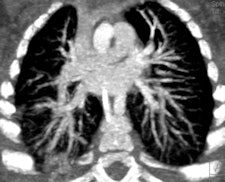

MDCT using a low radiation dose protocol is the best diagnostic tool for assessing the central airway, cardiovascular and mediastinal abnormalities, and the lung parenchyma in children, and the relevant information can be acquired with a single-volumetric data set acquisition, she stated. Using thin-slice collimation acquisition with inherent isotropic resolution, the image data can be manipulated and reformatted to display 2D and 3D images with the same spatial resolution as the axial images, thus enhancing diagnostic accuracy and providing data that can be used in presurgical planning and patient management.

Furthermore, wider coverage with faster tube rotation speeds has reduced overall imaging time, leading to a decrease in sedation needs, improved image quality due to reduction in motion and respiratory artifacts, and high-quality depiction of small vessels due to improved contrast enhancement as a result of higher contrast concentration over a shorter time period.